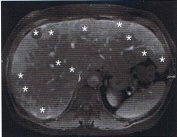

Standard in der Schnittbilddiagnostik ist die CT, die den Primärtumor in 22 – 45% der Fälle lokalisiert. Die CT-Diagnostik von Gastrinomen oder Insulinomen hängt maßgeblich von der Größe des Tumors ab, wobei Tumoren unter 1 cm Größe nur selten entdeckt werden. Für die Lokalisation von Insulinomen und Gastrinomen wird daher die Endosonographie empfohlen, die in der Hand eines erfahrenen Untersuchers als das sensitivste Detektionsverfahren angesehen wird (Sensitivität für duodenale NET 45 – 60%; für pankreatische NET 90 – 100%). Lebermetastasen zeigen in der CT häufig eine ausgeprägte Hypervaskularisation (Sensitivität >80%), die Sensitivität der Kernspintomographie ist noch etwas höher.